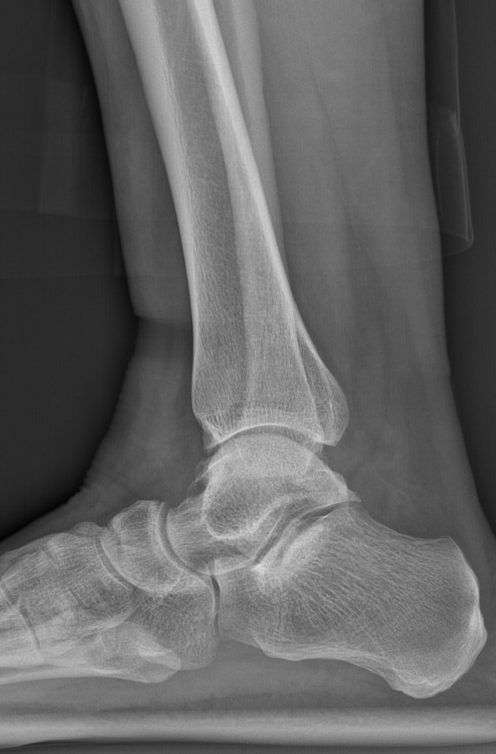

第一台手术的患者是位75岁的叔叔,被“脚脖子”痛缠了4年,疼得越来越厉害,病情已经到了严重阶段。

术前踝关节CT

术前后足力线X线

武勇主任团队给他做了3D打印导板辅助下人工全踝关节置换术。

这种手术适合踝关节病严重的患者,通过替换病变的关节结构,能帮着缓解疼痛、恢复关节活动,让老人日常走路更自在些。